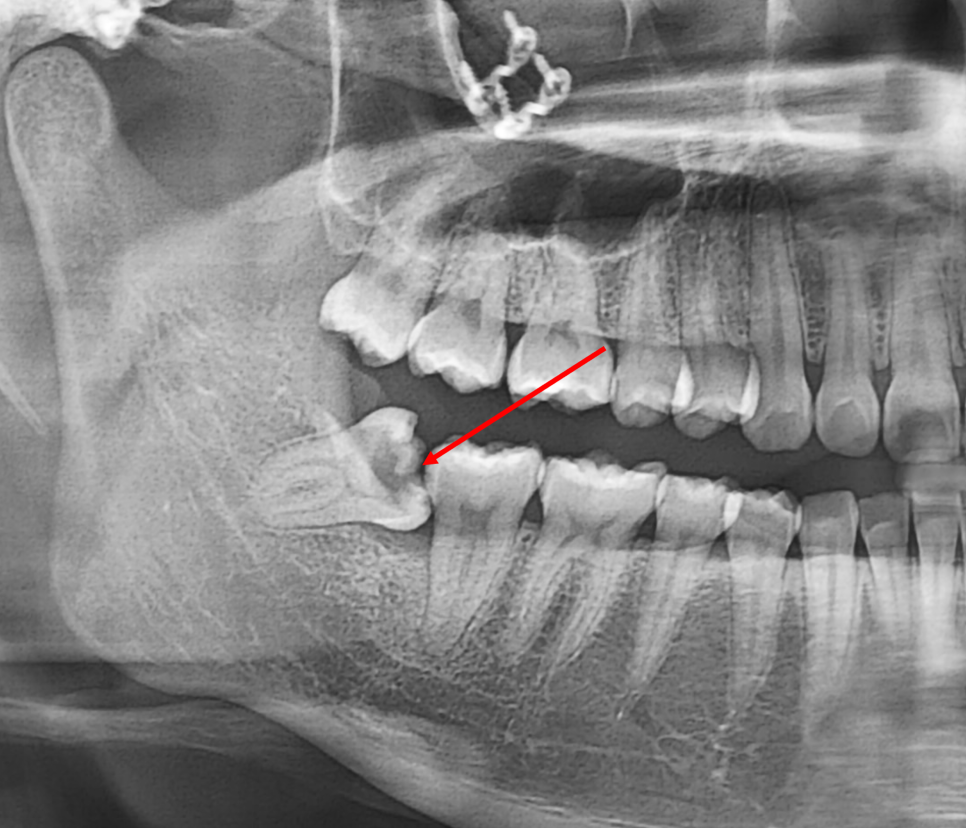

23.09.06(초진) – 24y 장OO님

아뿔싸..사랑니 머리의 충치가 너무 심해서

치아 안의 신경이 있는 곳까지 닿아있습니다.

(빨강색화살표)

아래턱뼈신경(빨강색화살표)과

사랑니뿌리(노랑색화살표)도 가까워서

발치 후 신경이 놀랄 합병증도 예상되는 바

더욱 신중하게 발치를 했습니다.